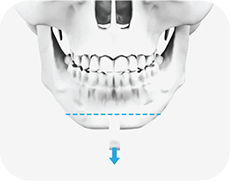

02

절골한 뼈의 가운데 부분을 제거